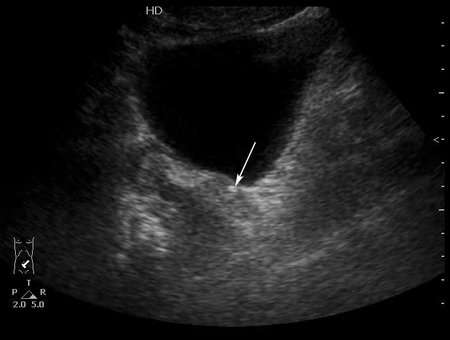

Конкремент в юкставезикальном отделе мочеточника. Пиелонефрит . Субкапсулярный выпот.

Да, МКБ,конкремент юкставезикального отдела мочетоника.

Выпот находится не под капсулой почки, а в периренальном пространстве в самой нижней точке человека прямоходящего.

Особенность этого случая заключается в том,что достаточно выраженные боли не сопровождались расширением ЧЛС, поэтому формула "отсутствие расширения ЧЛС на высоте болей практически исключает уретеролитиаз" здесь оказалась нерабочей.

Проводить инспекцию мочеточника пришлось из-за изменений почки - выпота и повышения эхогенности патенхимы. Как вариант рассматривался тромбоз ПА, но доплерографически он был исключен.

Не видите камня в юкставезикальном отделе мочеточника, предполагаете что это не камень и не в мочеточнике, считаете что это другая патология почки, - что смущает? )

Конкремент в юкставезикальном отделе мочеточника - стрелка.Брехт писал(а):Вокруг камни есть и отёчные стенки мочеточника?; или я допридумываю

Стенки мочеточника без существенных изменений.